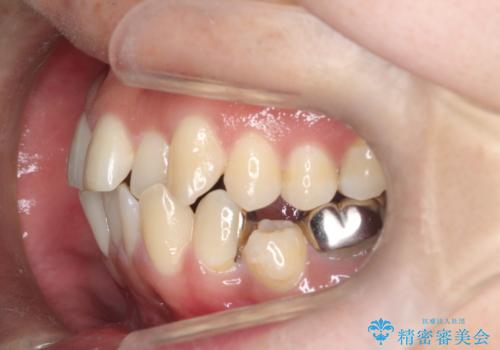

重度の叢生を抜歯矯正で改善|審美ワイヤー矯正+海外出張に伴う中断・再開対応

- 治療計画: 重度の叢生を改善するため、上下左右の小臼歯抜歯を伴う審美ワイヤー矯正を計画しました。抜歯により得られたスペースを利用して歯を整列させ、適切な噛み合わせを目指します。途中、患者様が1年間の海外出張となったため、一時的にワイヤーを外し、保定装置で現状維持を図りました。帰国後に再度審美ワイヤー矯正を再開し、仕上げ調整を行い治療完了を目指します。

重度の叢生により、抜歯を伴う矯正が必要と判断しました。目立ちにくい透明な審美ブラケットを用いたワイヤー矯正を実施しましたが、治療途中での海外出張が決定したため、一度矯正装置を取り外し、保定装置で現状維持を行いました。帰国後に改めて装置を装着し矯正を再開。患者様のライフスタイルに柔軟に対応しながら、最終的には理想的な歯並びと美しい口元を実現しました。